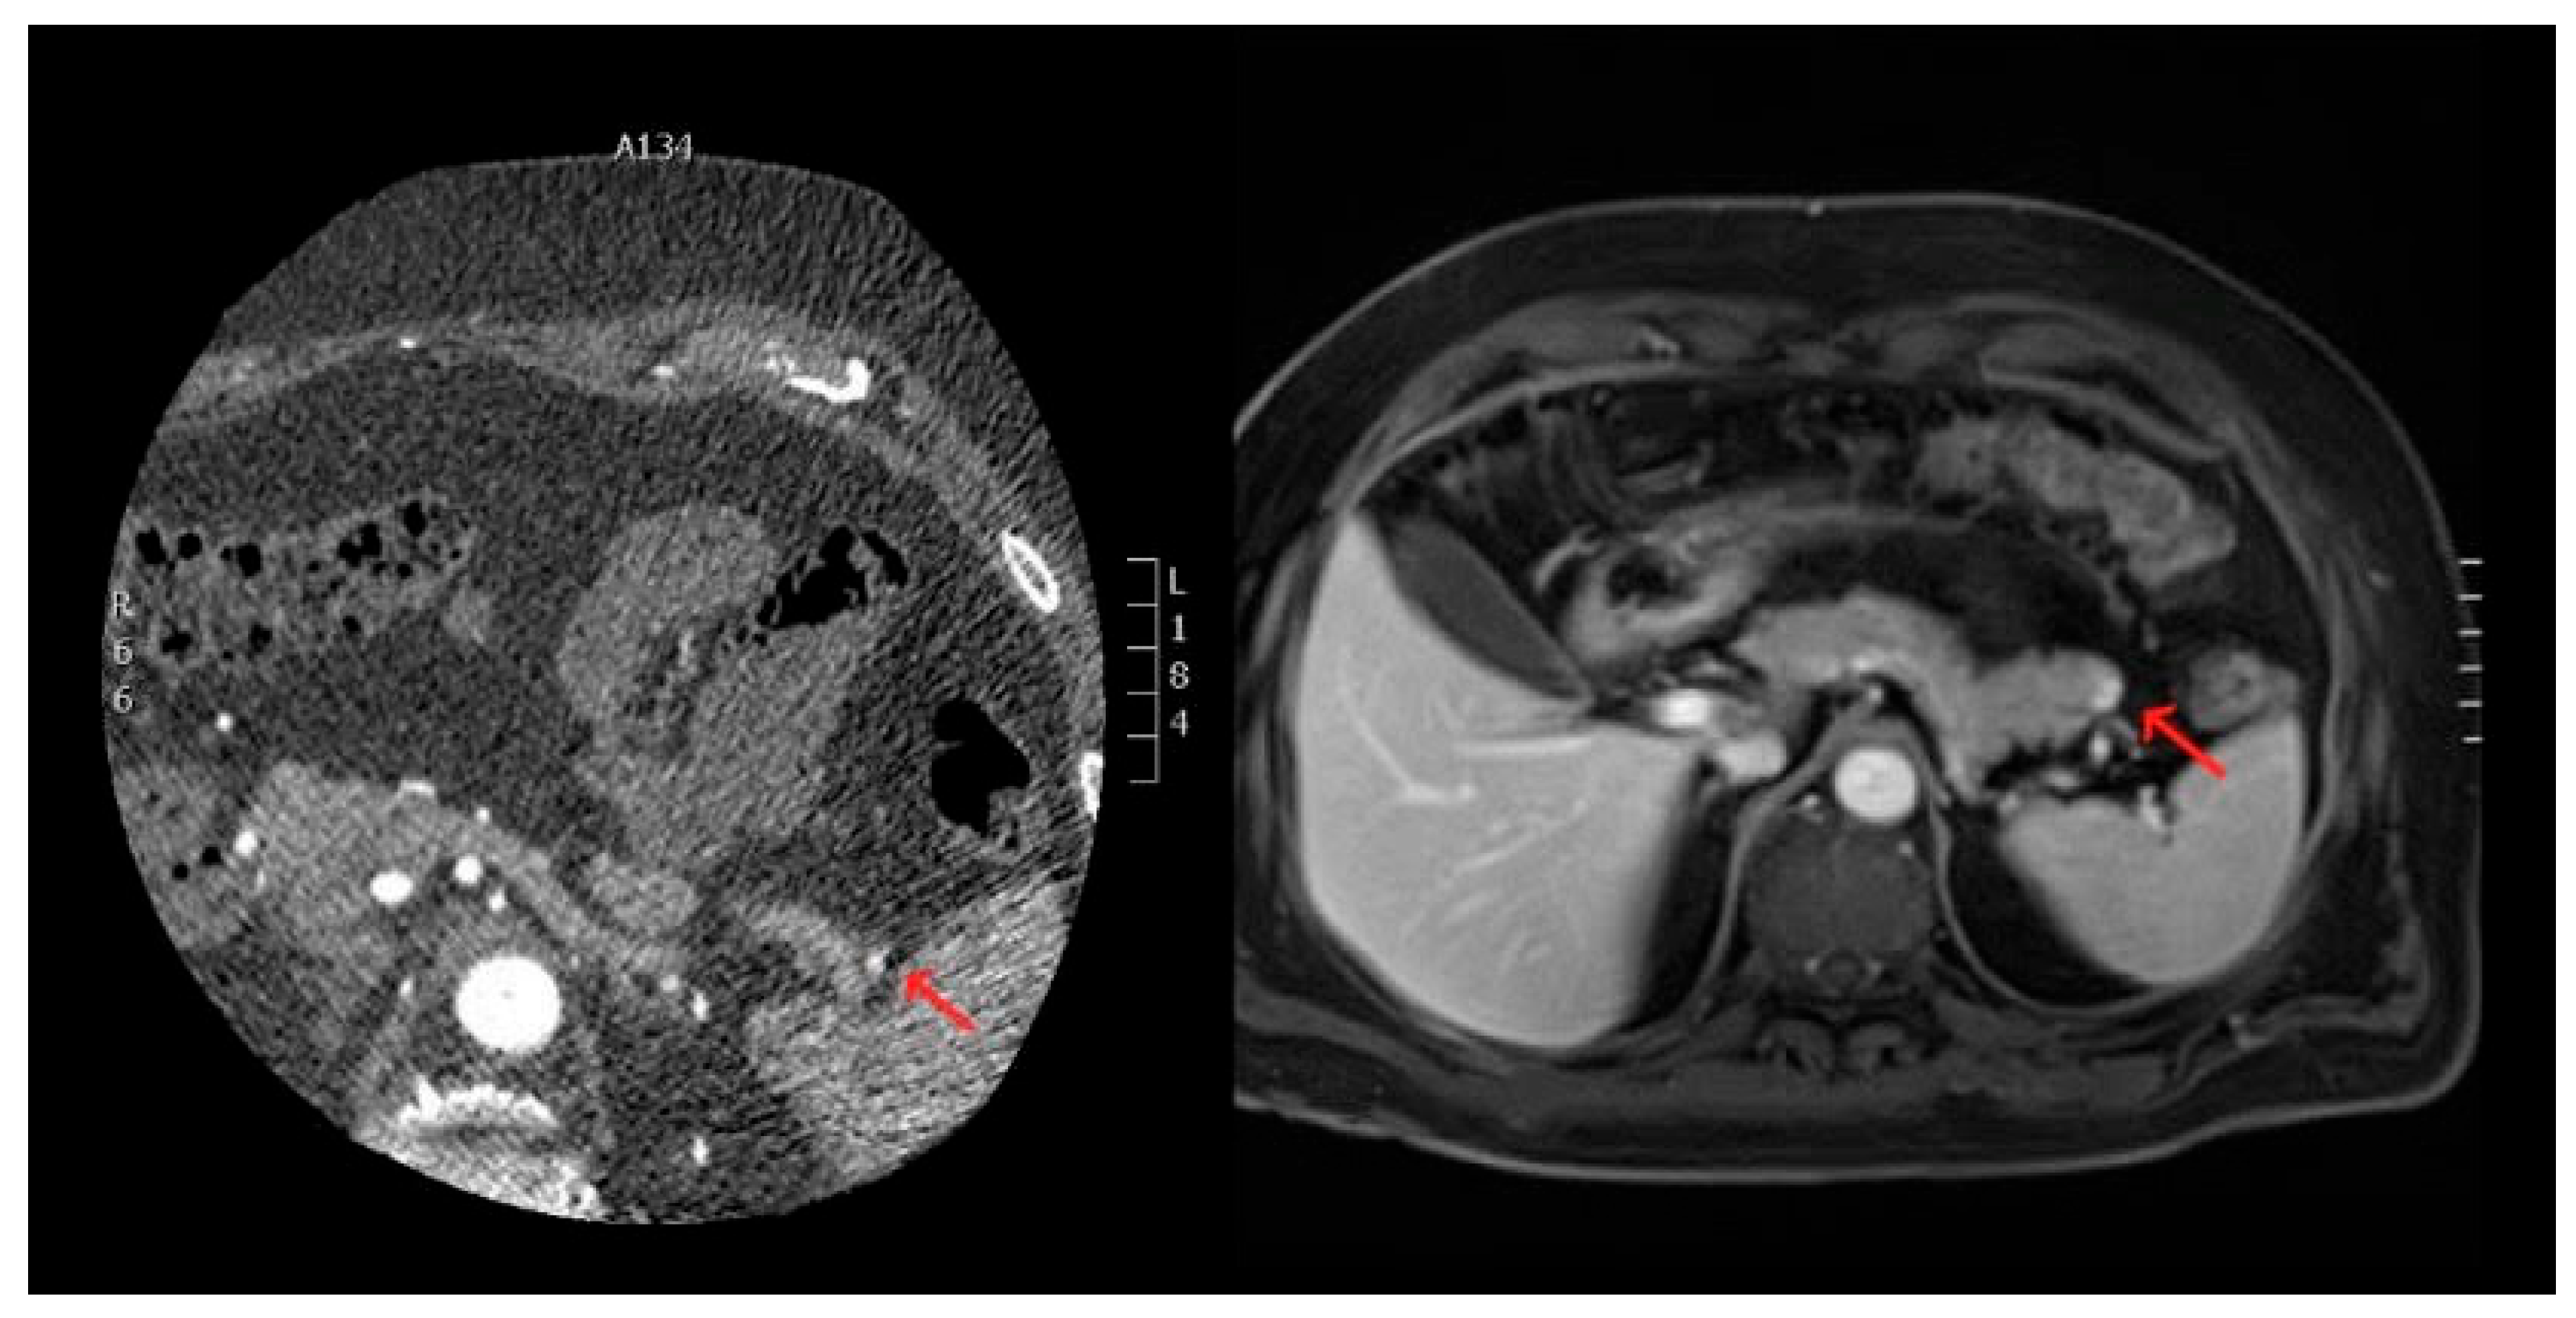

- Neoplastic Lesions in the Thorax and Upper Abdomen: Tumors or neoplastic growths were detected within the thoracic cavity and upper abdominal regions, such as the lung parenchyma and near the upper abdominal organs. These findings included both primary tumors and metastases (Figure 1).